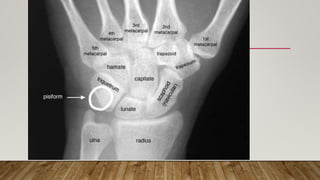

This document discusses radiology and the use of x-rays. It begins with an introduction to radiology and x-rays, noting their importance as the "father of medical investigations." It then discusses anatomy as seen on radiographs and whether x-rays are enough. The document goes on to compare gross views to radiological views, noting what each can and cannot show. It highlights important figures in the development of radiology, from x-rays to CT, MRI, and ultrasound. Specific anatomical structures visible on upper and lower limb x-rays are listed. The document concludes by discussing how pathologies appear on x-rays and the importance of clinical history and knowledge when interpreting radiological images.